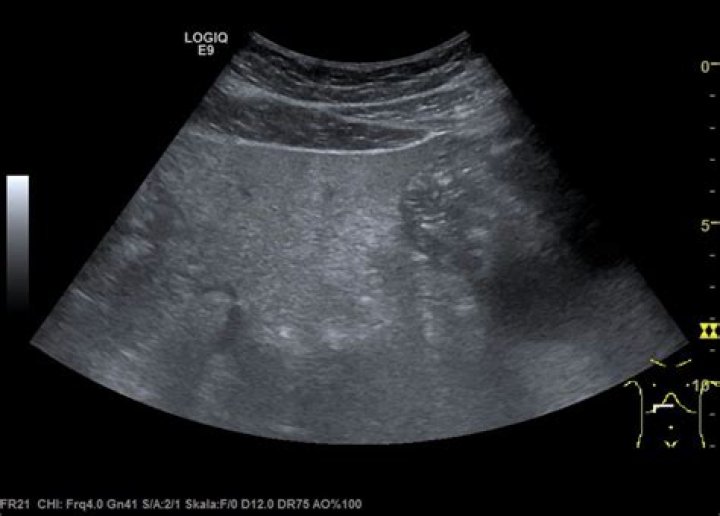

Sonographic findings of acute pancreatitis can be subtle and can include changes in pancreatic echogenicity, glandular enlargement, pancreatic duct dilation, and peripancreatic fluid [11]. Enlargement of the pancreas as well as hypoechoic or heterogeneous echotexture [8] is caused by associated interstitial edema (Fig.